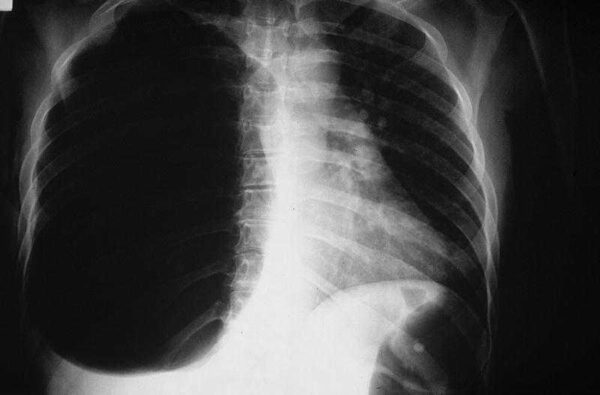

Los derrames pleurales se refieren a la acumulación anormal de líquido en el espacio pleural, que es la cavidad que rodea los pulmones dentro de la cavidad torácica. La…